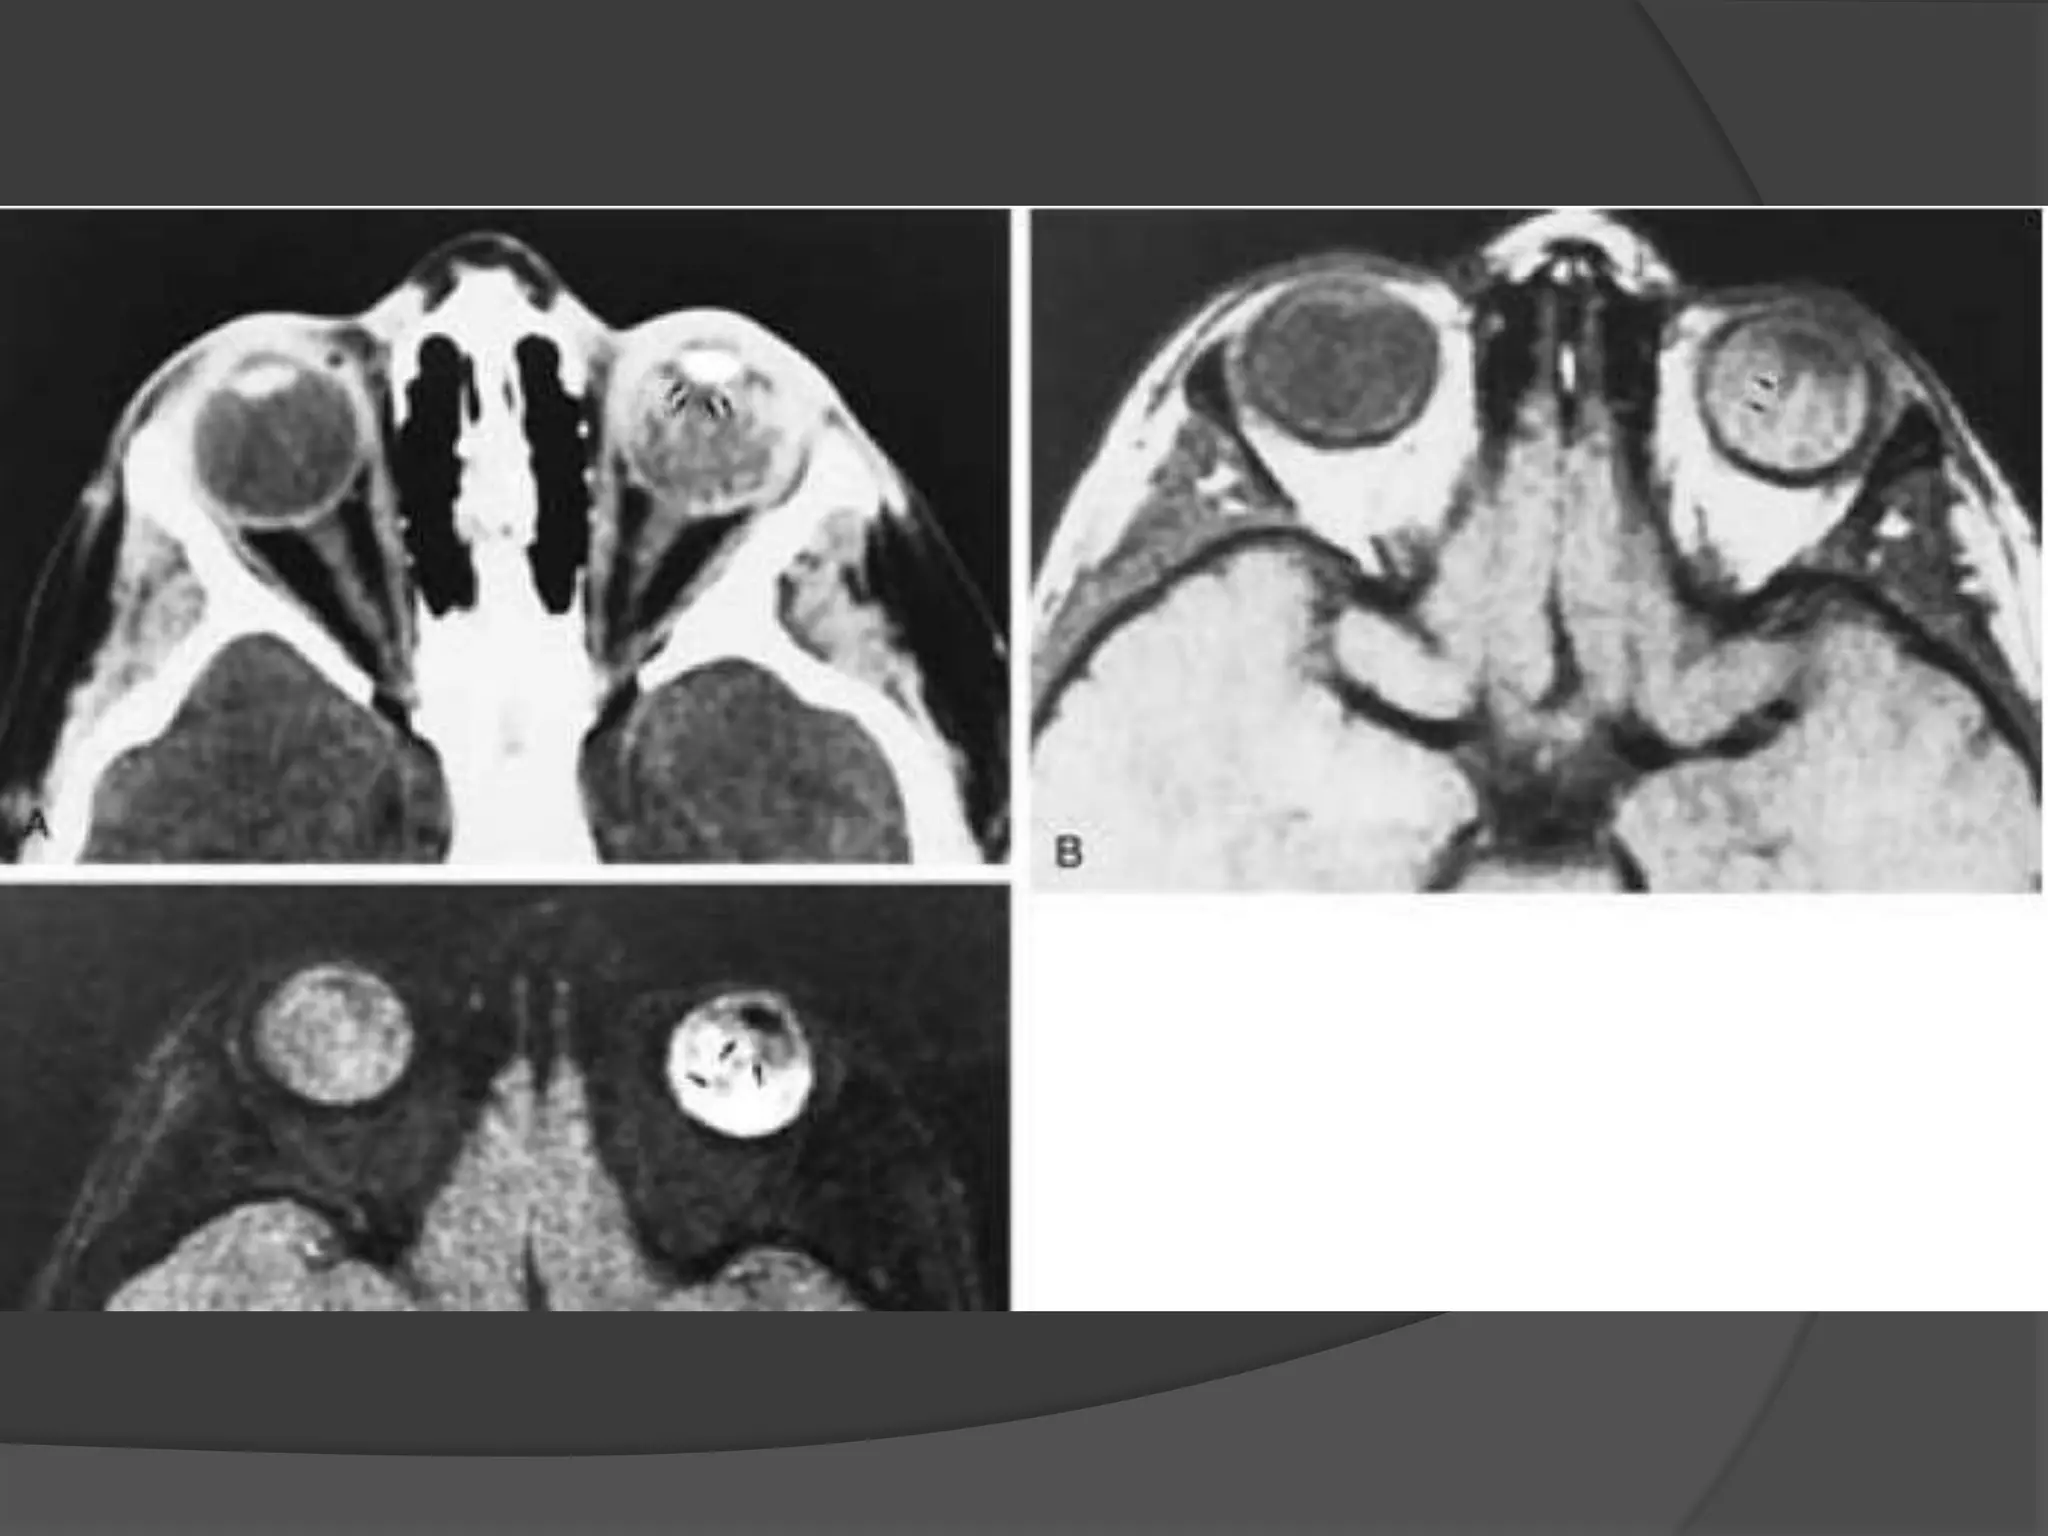

• #30 ROP. A, Axial CT scan shows increased density of the globes and left microphthalmos. B, Axial PW MR image shows hyperintensity of both globes, presumably caused by subretinal hemorrhage. Note the retrolental abnormal tissues (arrows) and detached retina (curved arrow). C, Axial T2-weighted MR image shows hyperintensity of the globes and abnormal retrolental soft tissues (arrows). Note the detached retina (curved arrow) and the layered acute hemorrhage in the right subretinal space (arrowhead ).